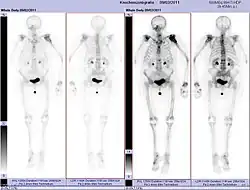

- Vues de fractures pathologiques

Fracture pathologique de l'humérus sur une métastase de carcinome du rein

Fracture pathologique du bras gauche sur une métastase osseuse de cancer du sein

Scintigraphie corps entier avec 99mTc-HDP de la patiente avec une fracture du bras due à une métastase du cancer du sein

Scintigraphie osseuse

La scintigraphie osseuse est actuellement encore le meilleur moyen de diagnostic des métastases osseuses. Ce procédé est relativement sophistiqué, coûteux et soumis à quelques limites diagnostiques[90]. Contrairement à la radio, on peut avec la scintigraphie représenter assez simplement l'ensemble des attaques du squelette[87]. Une scintigraphie osseuse est normalement bien plus sensible pour la détection des métastases osseuses qu'une radio. La sensibilité de la scintigraphie osseuse est assez élevée, avec 95 %. En moyenne, avec cette méthode, les métastases osseuses sont détectées six mois avant leur mise en évidence sur la radio[113]. Par contre la spécificité est substantiellement plus faible[114], car presque toutes les modifications tumorales ou inflammatoires du squelette conduisent à un enrichissement en radiotraceurs dans le voisinage. Le remodelage plus élevé et les processus de réparation dans la bordure des métastases osseuses ostéolytiques conduisent à une accumulation plus élevée du radiotraceur, visible comme un « point chaud » sur l'image de scintigraphie[115]. Un phénomène observable de rebond (flare up) peut être dû à l’augmentation de l’activité ostéoblastique au niveau des zones d’ostéolyse tumorale clinique, dont la colonisation métastatique a été éradiquée par le traitement ; il ne doit pas être confondu avec une progression métastatique, au risque de modifier le traitement de façon intempestive[116]. Dans les métastases osseuses de cancer du poumon ou du sein, la néoformation réactive d'os peut dans de rares cas être absente[117]. Sur la scintigraphie, ceci apparaît alors comme un « point froid », un domaine avec une absorption réduite du radiotraceur[118].

La scintigraphie osseuse est avant tout utilisée pour le contrôle de la thérapie, que ce soit une chimiothérapie, une radiothérapie externe ou métabolique, pour la détermination des stades, notamment pour les cancers avec tumeur primitive inconnue, et pour le suivi après cancer[87].